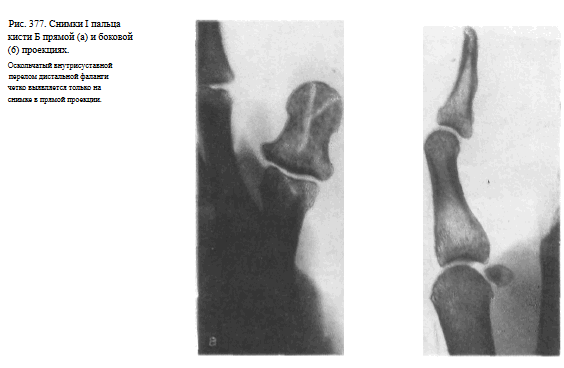

Видны наслаивающиеся друг на друга сесамовидные кости рядом с головкой I пястной кости (рис. 376). Снимки необходимо выполнять в двух взаимно перпендикулярных проекциях (рис. 377, а, б).